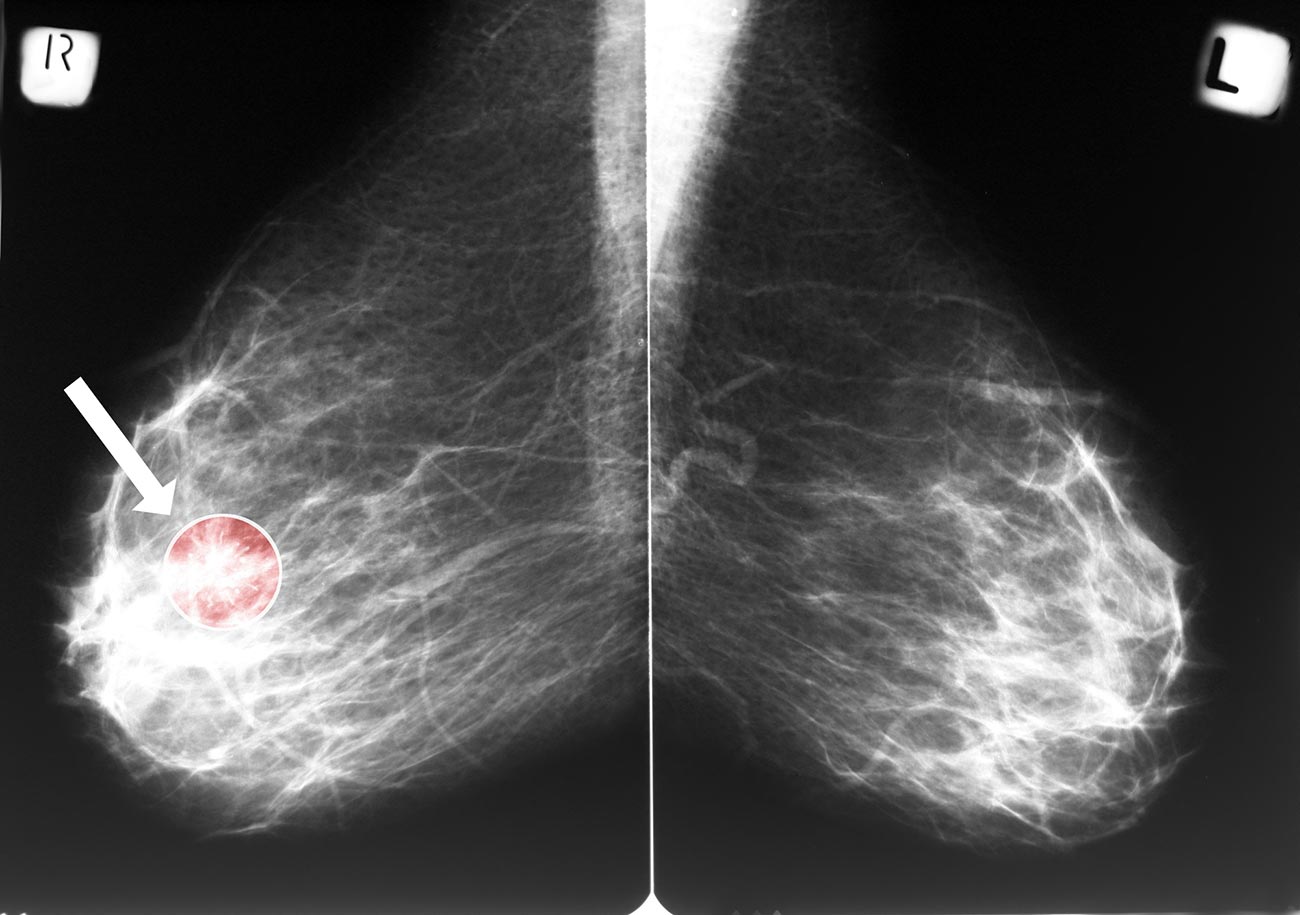

Фиброаденома молочной железы - доброкачественное образование, которое часто встречается у женщин. Оно может быть обнаружено при помощи различных методов диагностики, включая маммографию. Ниже представлены фотографии, помогающие понять, как выглядит данное заболевание.

Опухоль на снимке маммографии

Маммография и ее роль в диагностике фиброаденомы молочной железы

Маммография - это рентгенологическое исследование молочных желез. Оно позволяет выявить различные изменения в тканях, включая фиброаденому. На маммограммах можно увидеть структурные особенности опухоли и отследить ее динамику во времени.